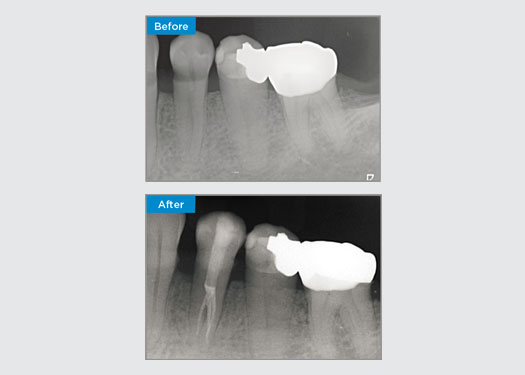

Deze patiënt presenteerde zich met een gebroken restauratie op tand 46 distaal-occlusaal aspect. De bestaande restauratie van de tand reikte zeer diep en dicht bij de pulpakamer. Gezien de grote omvang van de restauratie was het zeer waarschijnlijk dat als we de restauratie gewoon zouden vervangen door een andere directe restauratie, het resultaat hetzelfde zou zijn, waarbij de restauratie onder de occlusale belastingen breekt waaraan de tand en de restauratie worden blootgesteld. Er werd dus een indirecte optie aanbevolen voor de tand. Aangezien het mesiale derde deel van de tand grotendeels niet werd beïnvloed door de resterende substantiële gezonde tandstructuur, konden we deze behouden en minimaal invasief zijn door de tand te herstellen met een indirecte restauratie met behulp van het CEREC-systeem

Dr. Sahil Soni, Queensland, Australië